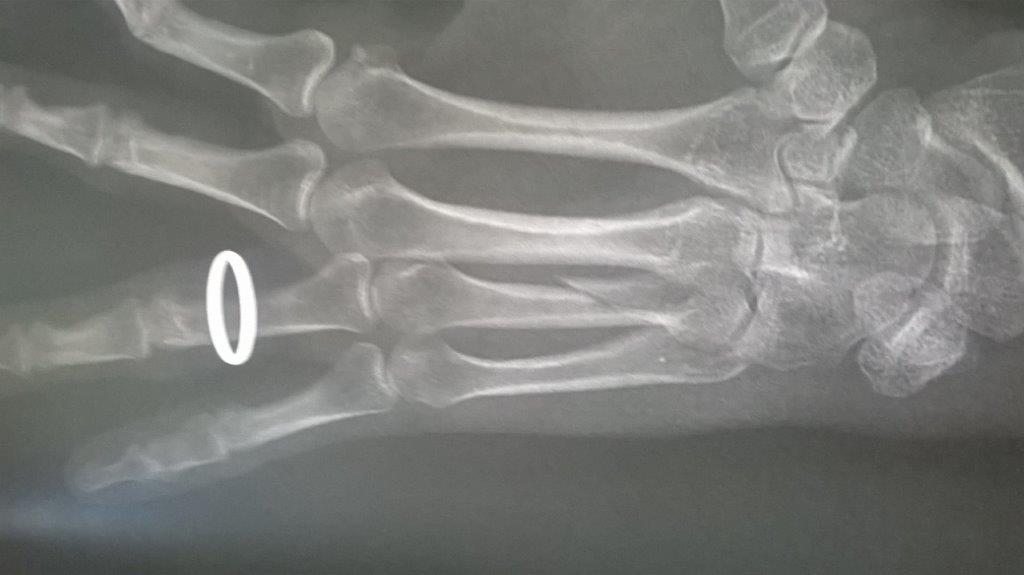

Résultat : fracture de la main gauche

Fichier(s) joint(s):

WP_20170914_001.jpg [ 47.5 Kio | Vu 32764 fois ]